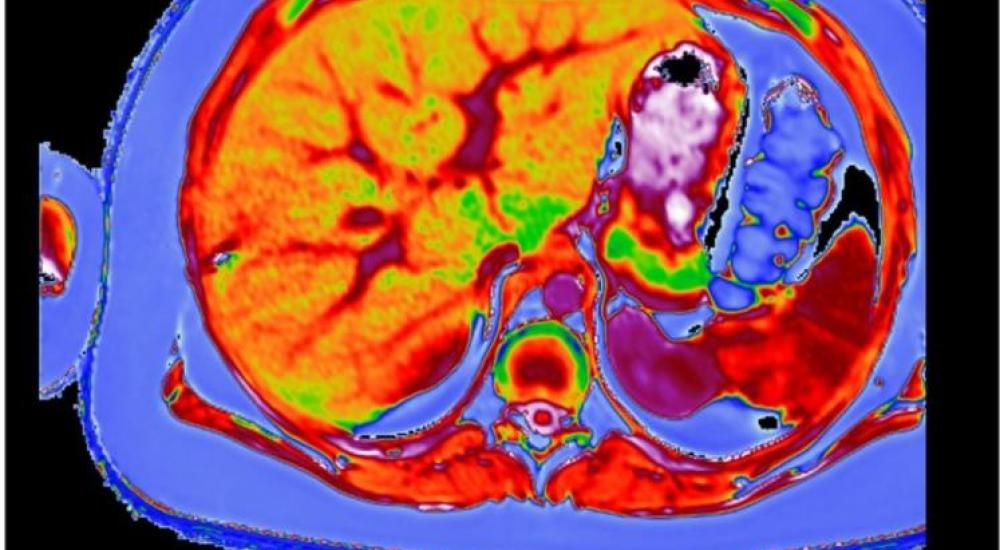

أظهرت دراسة حديثة أن بريطانيا تشهد ارتفاعا وبائيا في مرض الكبد الدهني غير الناجم عن الخمر (non alcoholic fatty liver disease)، في وقت يتناول فيه الناس كمية من الطعام أكبر مما تستطيع أجسامهم التعامل معها، ونشرت الدراسة من قبل الاتحاد الأوروبي.

ويقدر أن مرض الكبد الدهني غير الناجم عن الخمر يؤثر في نحو ثلث سكان بريطانيا، وأن الكثيرين من المصابين لا يعرفون أنهم مصابون بالمرض.

ويعد المرض أحد المسببات الخمسة الأولى للموت في بريطانيا، بالإضافة إلى السرطان ومرض القلب والسكتة الدماغية.

ولا يؤثر المرض في الأشخاص البدناء فقط، بل يشمل أيضا الأشخاص الذين يعانون من زيادة بسيطة في الوزن.

ويقول المختص في أمراض الكبد كوانتين أنستي إن المرض يرتبط بالطعام والإفراط في الأكل، مضيفا أنه يؤثر في 94% من الأشخاص البدناء، وفي 25% من الذين يعانون من زيادة بسيطة في الوزن.